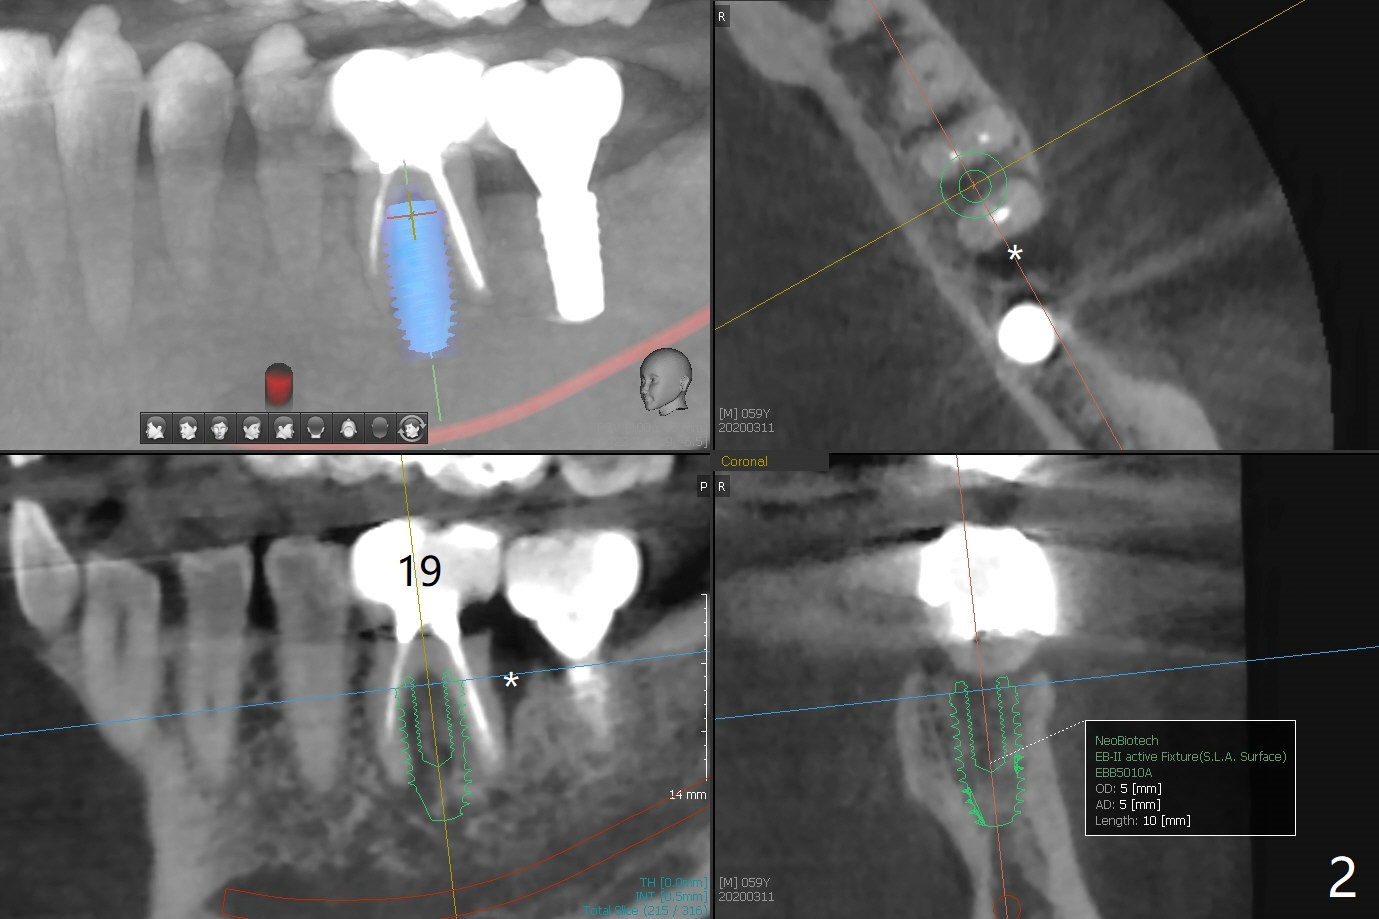

A 59-year-old man returns from endo-dontist office with diagnosis of "root fracture" of #19 (Fig.1).  The distal pockets are 5 mm deep with tender-ness, associated with bone loss (Fig.2 *).  Imme-diately post immediate implant placement, PRF or GEM21S mixed with cortical allograft will be used for bone regeneration.   Prior to bone graft, place an abutment, take a PA and make sure that the abutments at #18 and 19 are completely seated.  Reseat or trim the crestal bone if needed.   Prepare bleach gauze.  PRF will be used for sticky bone, which is more retentive than allograft hydrated with GEM21S.